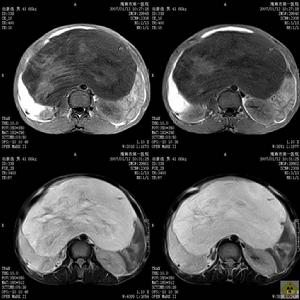

淋巴肉瘤淋巴肉瘤少見,占腦瘤的0.8~1.5%,成年男性(50~60歲)發生率較高。有惡性淋巴瘤、網狀細胞肉瘤、惡性網狀細胞增殖症、網狀組織細胞性腦炎、不典型肉芽腫性腦炎、淋巴增生性疾病等各種命名。反映了本瘤的組織發生學及組織學尚認識不足。本瘤病因不詳,大多認為發生於血管周圍的未分化多能細胞,由於某種因素(如外傷、抗原)刺激,此細胞可分化為血細胞,包括淋巴細胞並可能發展成為淋巴肉瘤。近年來由於進行腎移植手術,套用免疫抑制劑及患獲得性免疫缺陷疾病(Aids)增多,因而造成抗腫瘤免疫監視功能減弱,有利於此瘤發生,發病率有增多趨勢。腫瘤呈單發或多發。分布於基底節、胼胝體、腦室周圍、丘腦、大腦半球白質及腦幹等處,少數可浸潤硬腦膜、蛛網膜。瘤細胞為短梭形並以血管為中心排列呈花圈狀、袖套狀或簇狀生長,致使血管內腔變細、閉塞,產生小灶出血、壞死。

淋巴肉瘤圖治療

治療可作手術切除但療效差,放療及化療可以提高療效。常用60Co全腦照射劑量(40~50Gy)。腦脊液中找到瘤細胞者應加作脊髓補充照射。常用化療藥物有阿黴素、博萊黴素、氨甲喋呤(MTX)、阿糖胞苷(Ara-C)、環磷醯胺、長春新鹼等。